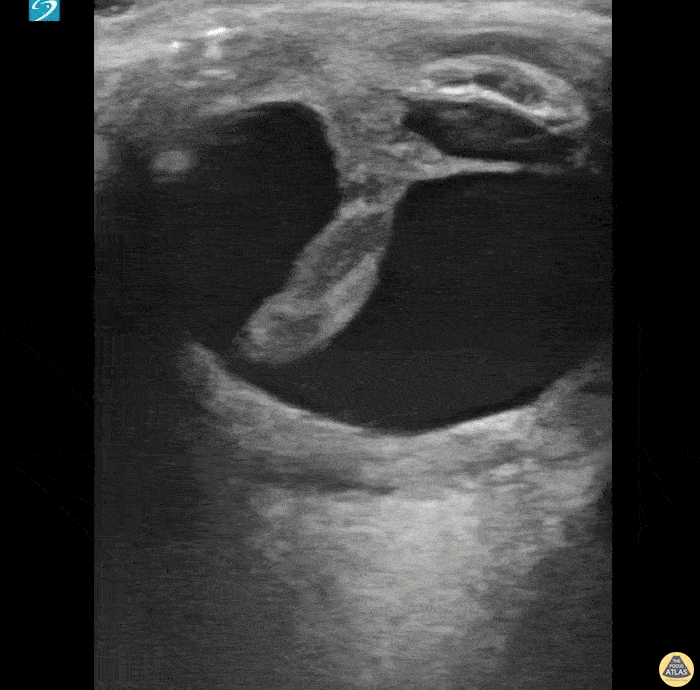

Orbital - Old Globe Rupture

Irregularly shaped eye with internal dense structure concerning for intraocular hematoma. This patient had a history of previous rupture of the globe. A CT Head without IV contrast described the left eye as follows: Small left globe with high density concerning for intraocular hemorrhage. Direct examination is recommended. Halimah Hamidu-Egiebor Central Michigan University College of Medicine MD-MBA '24, Arthur Sieron Central Michigan University Emergency Medicine Resident, Eric 'Dax' Spencer Central Michigan University Emergency Medicine Resident